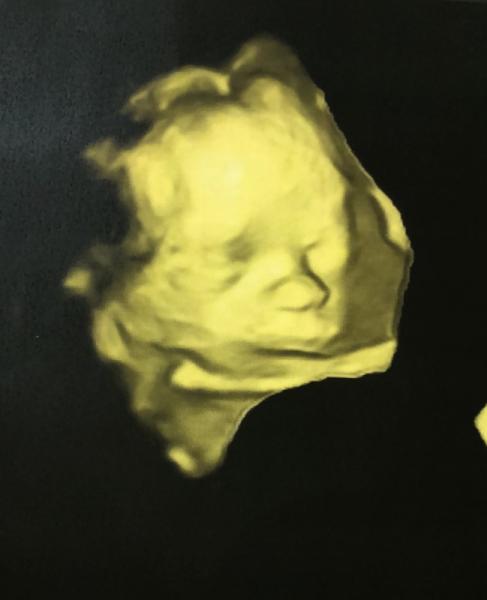

Und hier noch das neuste Bildchen Ich bin schon sehr verliebt

Auch sehr sehr süß Wahnsinn wie sehr man schon verliebt sein kann

Wunderschönes Foto Schön, dass alles gut ist!